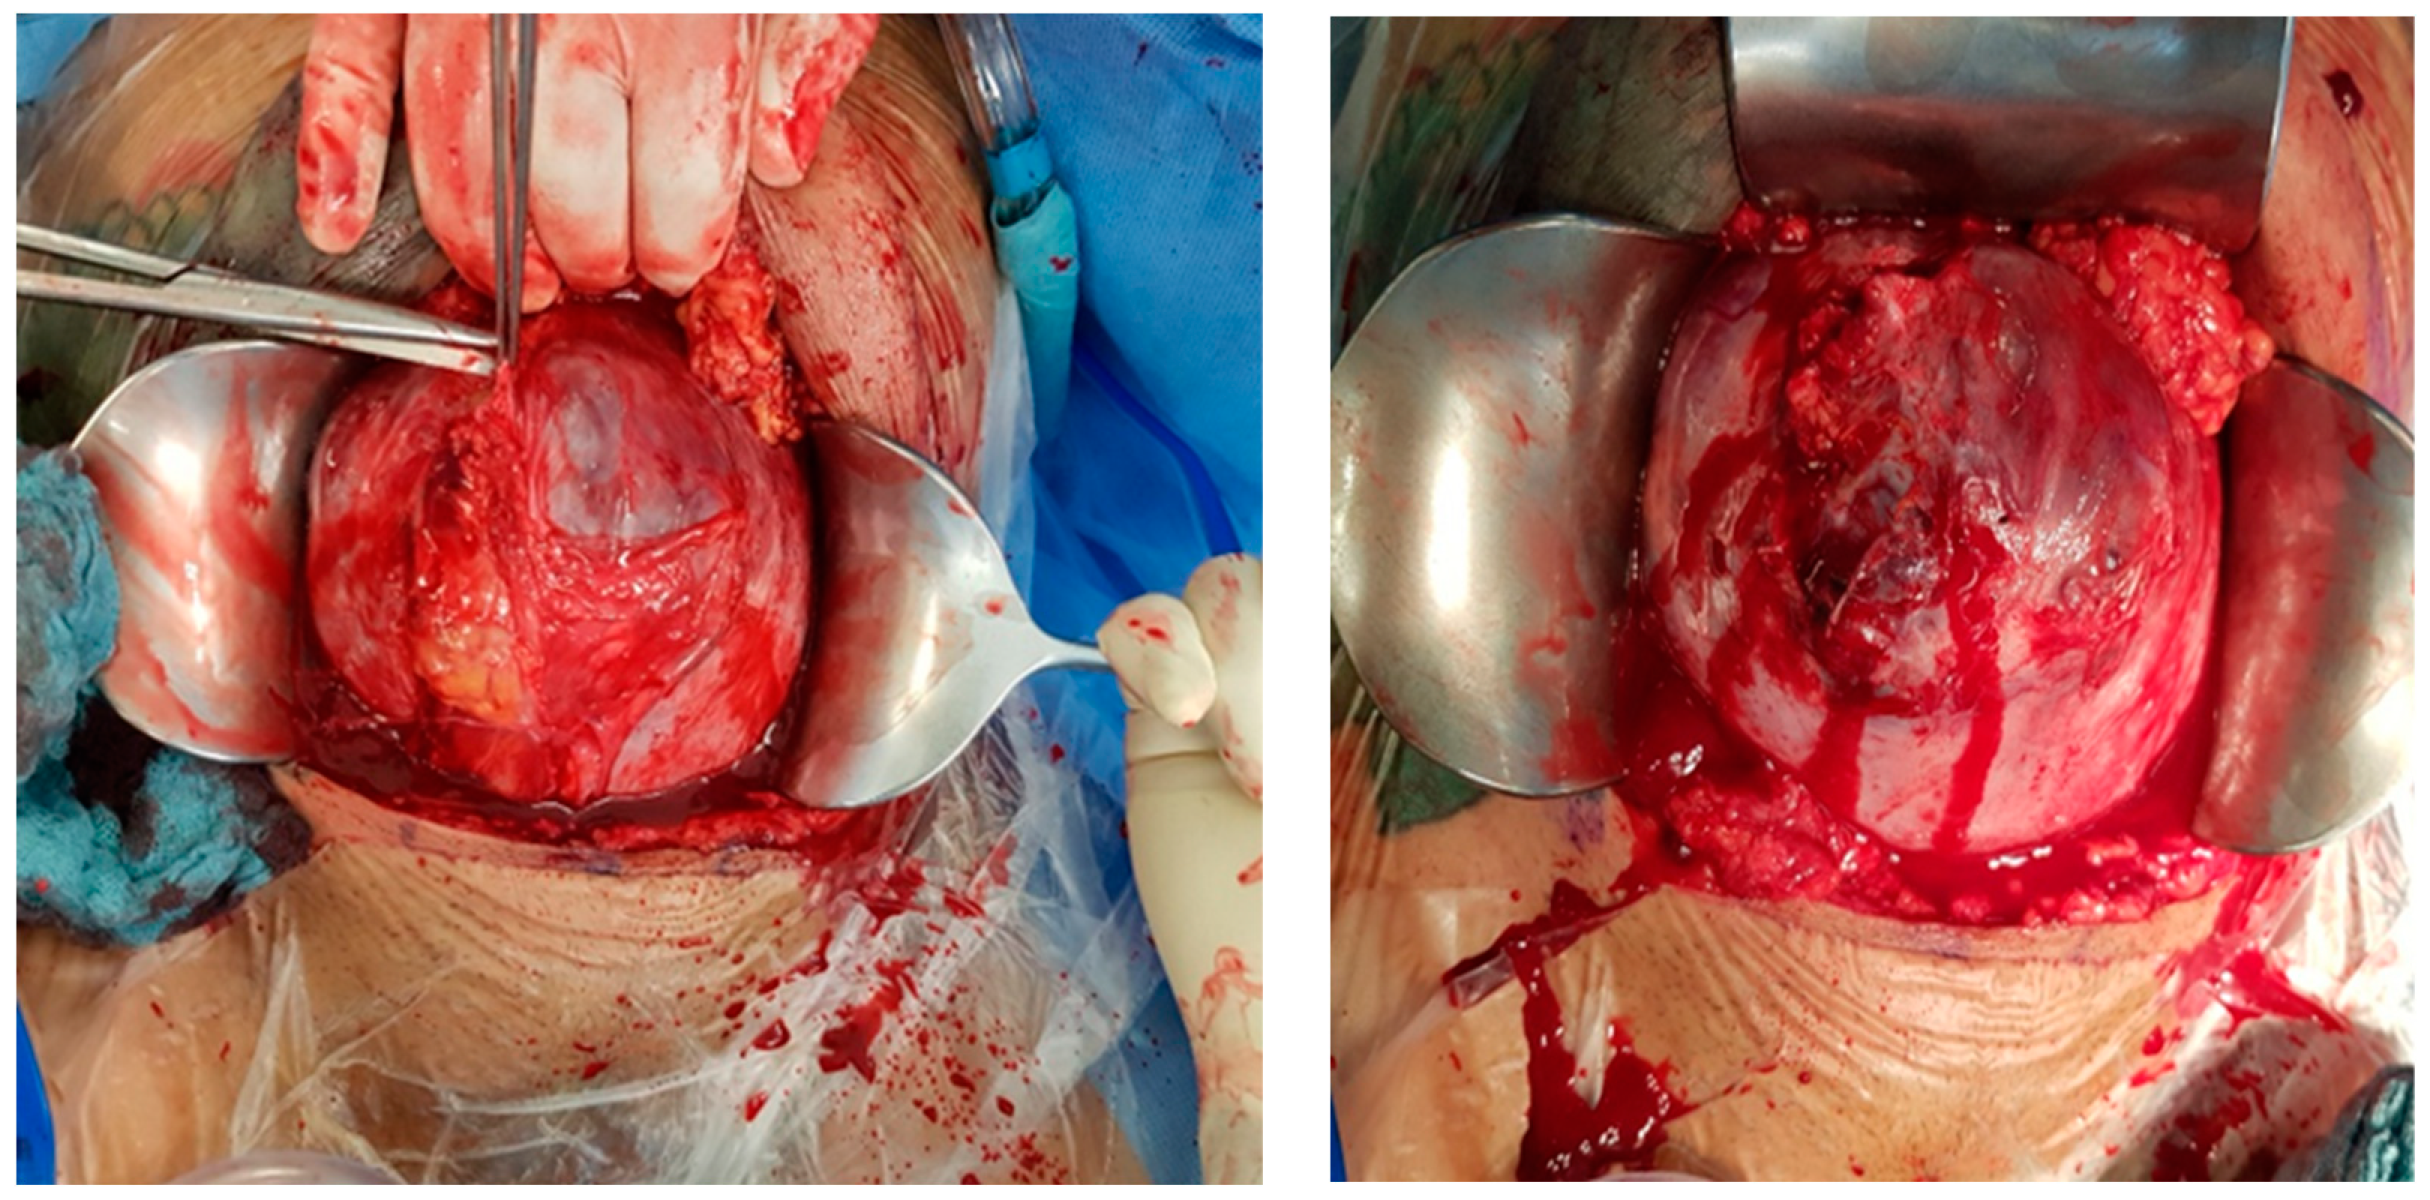

Intraoperative findings (Figure 8):

Figure 8.

Depict the uterus during and after hysterectomy performed for placenta increta.

Intraoperative findings (Figure 10):

Figure 10.

depict the uterus after hysterectomy with placenta previa and increta extending to the serosa. These images show the following findings:

- The uterus following a hysterectomy illustrates the presence of placenta previa with increta extending to the outermost layer of the uterine wall (serosa).

This confirms the suspected diagnosis of placenta previa with placenta increta, which necessitated the hysterectomy procedure to manage the condition.